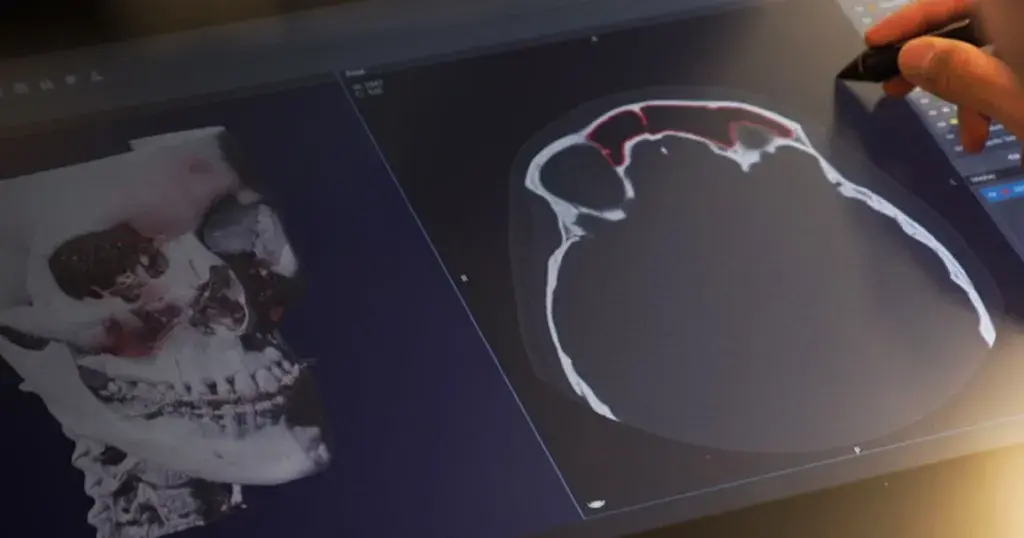

The ability to print patient-specific instruments and devices on demand and on-site is revolutionizing healthcare. By bringing 3D printing and procedural planning technologies to the point-of-care, healthcare providers are improving outcomes1, 2, increasing efficiency4, and lowering the cost of care5. Additionally, hospital operations are discovering that additive manufacturing can help fill supply chain gaps, enabling the production of needed medical supplies on demand.

Craniomaxillofacial, orthopaedics and radiation oncology are just a few of the specialties in which 3D printing at the point-of-care can expedite patient-specific procedures. Applications include: